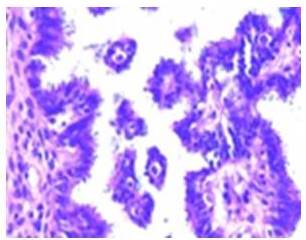

Paciente de 53 años de edad, III gestas, III paras, quien refiere aumento de volumen en hipogastrio, progresivo de seis meses de evolución motivo por el cual acude al Centro Médico Docente la Trinidad, donde es evaluada. Al examen físico: paciente en buenas condiciones, masa abdominal palpable desde hipogastrio que sobrepasa cicatriz umbilical, móvil, no dolorosa, aumentada de consistencia. Dentro de los estudios paraclínicos, se encontró un Ca125: 325 U/mL, resto sin alteraciones. Se solicita tomografía de abdomen y pelvis con doble contraste, evidenciando un LOE de gran tamaño (Figura 3). Paciente es intervenida quirúrgicamente, se le practicó una incisión de Maryland, evidenciando como hallazgo intra-operatorio: tumor de ovario izquierdo gigante, con infiltración macroscópica de superficie ovárica (Figura 4), se procede a realizar protocolo de ovario. El resultado patológico obtenido fue biopsia ovario izquierdo: tumor seroso papilar borderline (de bajo grado de malignidad) con foco de micro-invasión menor a 1 mm, tumor seroso borderline en superficie ovárica - cuerpos de psamoma. Biopsia ovario derecho: tumor seroso papilar borderline - cuerpos de psamoma. Epiplón mayor: implante superficial no invasivo de tumor seroso borderline, fondo de saco anterior: implante no invasivo de tumor seroso papilar borderline. Resto de las muestras sin alteraciones. Paciente no recibe quimioterapia. Se observa disminución de Ca125 hasta su normalidad y ausencia de enfermedad en estudios radiológicos de control. Actualmente sin evidencia de enfermedad, seis meses pos operatorio.